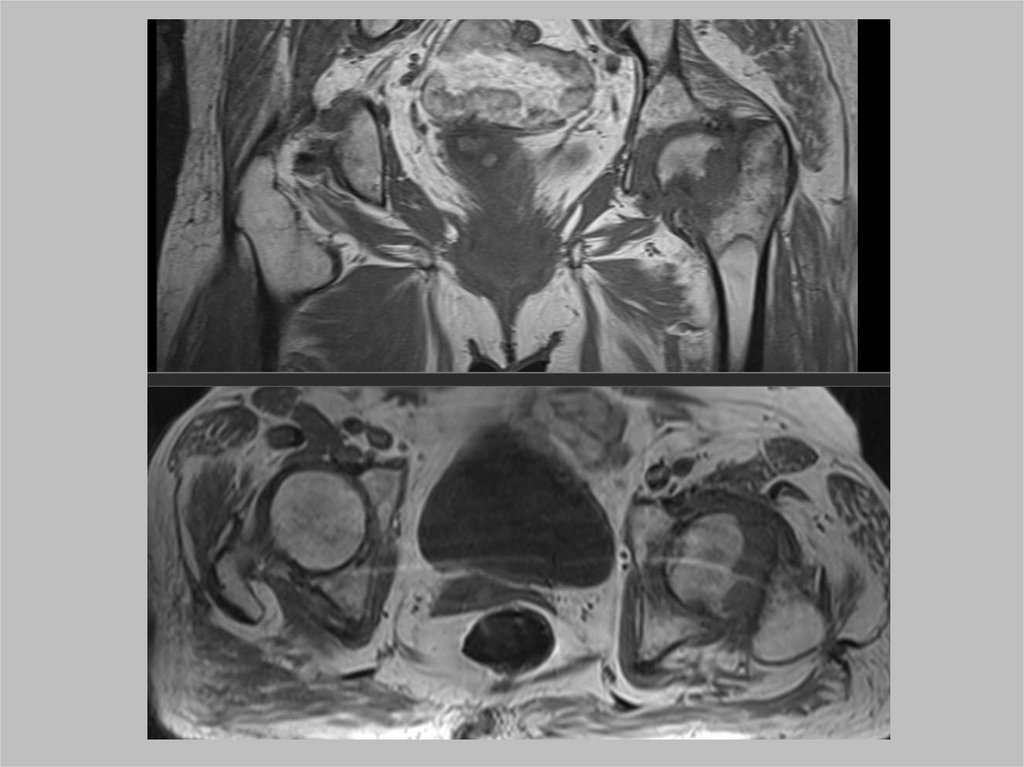

Опухоли в области

тазобедренного сустава

Костные

Доброкачественные

• Остеома

• Остеохондрома

• Энхондрома

Злокачественные

• Остеосаркома

• Саркома Юинга

Не опухоли

• Эностоз

• Костные кисты

• Фиброзная дисплазия

Мягкотканные

• Липома

• Десмоидная

• Гибернома

• Гемангиома

• Липосаркома

• Мезенхимома

• Саркома

• Гематома

• Гамартома